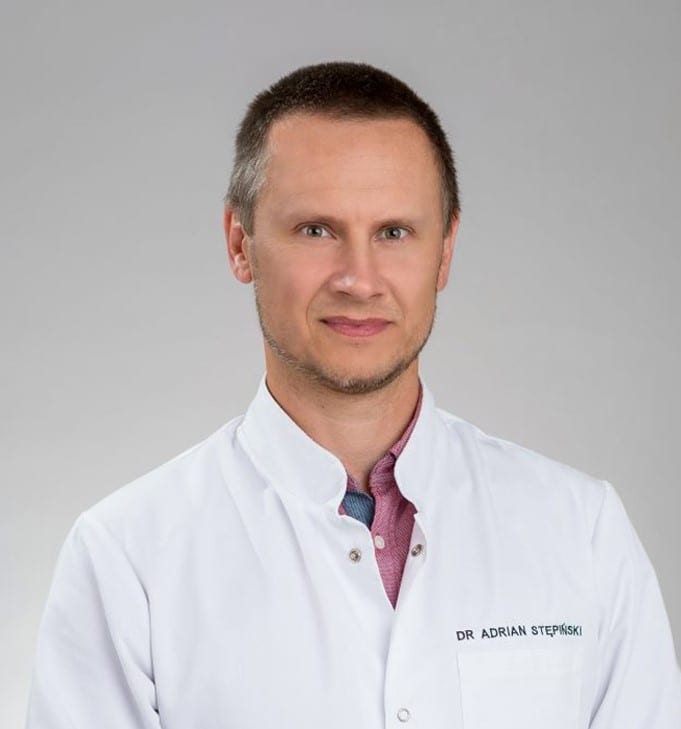

Ortopeda dziecięcy to lekarz specjalizujący się w diagnostyce i leczeniu chorób oraz urazów układu ruchu u dzieci i młodzieży. Zajmuje się m.in. wadami wrodzonymi kończyn, nieprawidłowościami w budowie narządu ruchu, wadami postawy czy urazami, takimi jak złamania i skręcenia.

W neoMedica w Poznaniu działa gabinet ortopedii dziecięcej, w którym konsultowane są dzieci w każdym wieku. Oprócz oceny i leczenia lekarz ortopeda dziecięcy wykonuje także badania ultrasonograficzne (USG), pomocne w diagnostyce wielu schorzeń ortopedycznych.

W neoMedica w Poznaniu ortopedzi dziecięcy przyjmują pacjentów prywatnie, oferując diagnostykę i leczenie schorzeń układu ruchu u dzieci w różnym wieku. Podczas wizyt zwracają szczególną uwagę na potrzeby najmłodszych pacjentów, łącząc badania i konsultacje z empatią oraz podejściem dostosowanym do dziecka.